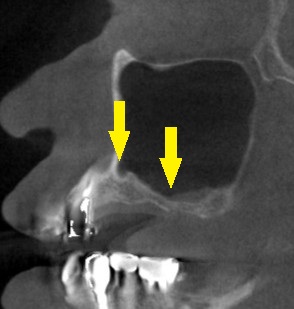

インプラント治療であれば、4歯ないところへ、2本のインプラントを埋入して、3歯回復を目指したいのですが、CTで見ると、特に2本目のインプラントを埋入したいところは、骨が非常に薄い状態でした(下の写真上段右)。

ワイドインプラントでも対応が困難と考え、サイナスリフトという骨造成をまず行って、骨量を確保することを提案させていただきました。